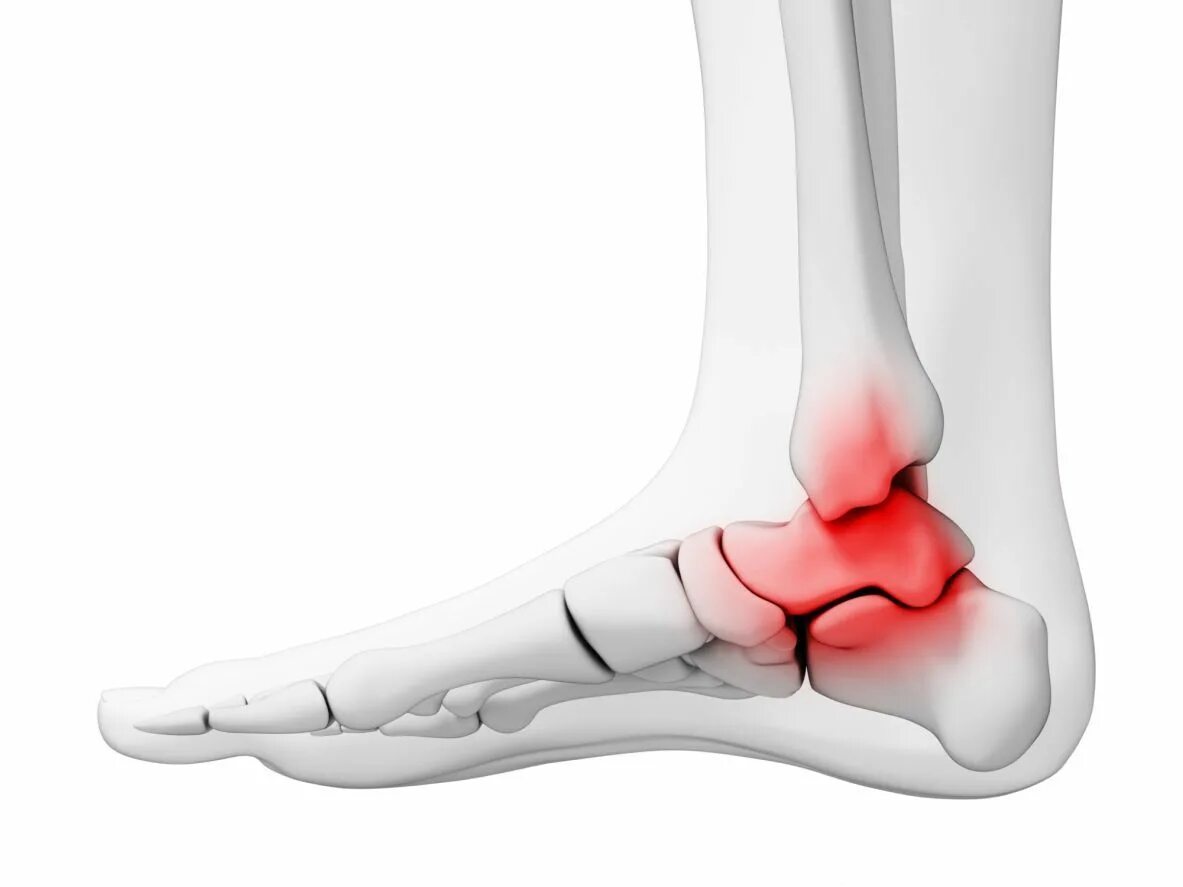

Артроз голеностопного сустава код